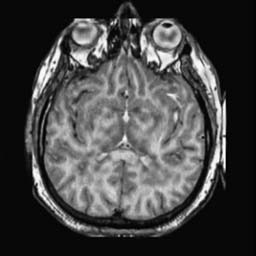

To demonstrate the effectiveness and efficiency of the proposed image fusion method , we conduct a set of comparative experiments on three image datasets. The first is composed by 8 pairs of multi-modal medical images and the second one contains 15 pairs of multi-focus gray or color natural images. These two datasets are often used in many related papers and some examples are shown in Figure 3(a) and Figure 3(b). The third one is a new multi-focus cervical cell image dataset collected by ourselves, which consists of 15 groups of color images and each group contains a series of multi-focus cervix cell images with size of or , etc. Some source examples are shown in Figure 3(c). Our source code implemented in C++ along with the new multi-focus cervical cell image dataset is available online.

We first evaluate the performance of the proposed method under varying total number of octaves and number of layers sampled per octave. The fused images of a pair of multi-modal medical images with different and are shown in Figure 4. In this example, on the one hand, when only 1 or 2 octaves are involved in constructing the DoG pyramid, the fused images fail to keep the integrity information of large size objects (e.g. eyeballs), while by increasing the value of , the integrity information of eyeballs is preserved. On the other hand, although not as significant as the increase of octave numbers , the fused image can contain more details by the increase of layer numbers . The corresponding objective quality metrics are shown in Figure 5. As shown in Figure 5(a), most of the metric values are improved as the number of octaves increases with the fixed layer numbers 3 in the global tendency and each of them tends to be stable when the number of octaves is 5. To get a relatively good quality from Figure 5(b), we can notice that some of the metric values can get a good performance when the number of layers is 3, such as the MI, SSIM, QI and VIF, though there are only a little change of all the metric values by increasing the number of layers with the fixed octave numbers 5. Because it will result in more computation burden with the increase of the value and , and for different kinds of source images, there are different performance with the diverse parameter settings. To get a trade-off between them in our experiments, we set for the multi-modal dataset, for the natural datasets and for the multi-focus cell dataset, respectively.

Figure 6 shows the fused images obtained by different methods with the multi-modal source images shown in Figure 3(a). As shown in these figures, the proposed method can produce images which preserve the complementary information of different source images well. Moreover, due to the scale-invariant structure saliency selection, our method can keep the integrity information of large size objects and the visual details simultaneously. Although the fused image generated by other methods can also capture the details to some extent, all of them fail to keep the integrity information of large size objects such as the eyeballs. Furthermore, from Figure 6(k)-6(t), the DTCWT, GFF, IM and NSCT methods may decrease the brightness and contrast while the proposed method can preserve these features and details without producing visible artifacts and brightness distortions.